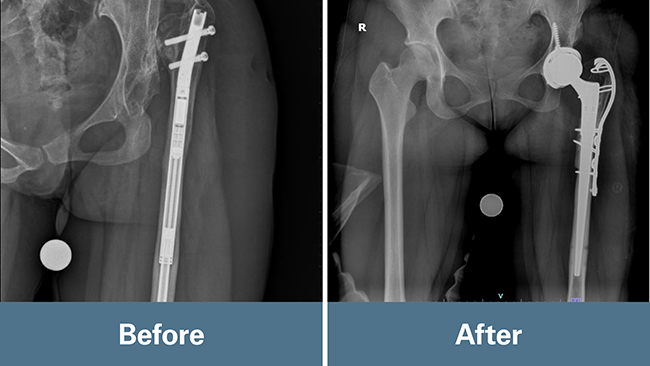

“It’s atypical based on the original orthopedist years ago putting a revolutionary growing nail (metal rod) into her femur, with the idea it would provide some benefit in the short run,” Schroder said.

At age 15, Anh underwent a nine-hour leg lengthening surgery as a temporary measure until she stopped growing and a hip replacement could be done. At the time, lengthening her femur bone was a first-of-its-kind procedure at the hospital where it was performed.

“A lot of engineering and math went into our surgery because we had to determine Anh’s actual leg length discrepancy and how much bone we needed to subtract from her femur to match the femur length on the other side,” Schroder said. “It ended up being about 4 centimeters.”

Schroder said the surgery would entail a long day with unknowns and thinking on the fly. Thankfully, it went as planned for her and the surgical team. They did a large release of the capsular tissue from the top of the hip, removed the femur rod, and subtracted the prescribed amount of bone. They placed the implant in the bone and the shaft of the bone to build the replacement back up to the normal femur length.